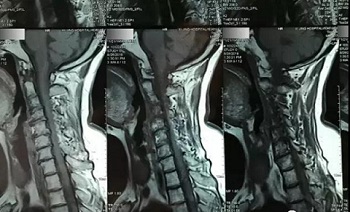

(区域4)

(区域5)

(区域6)